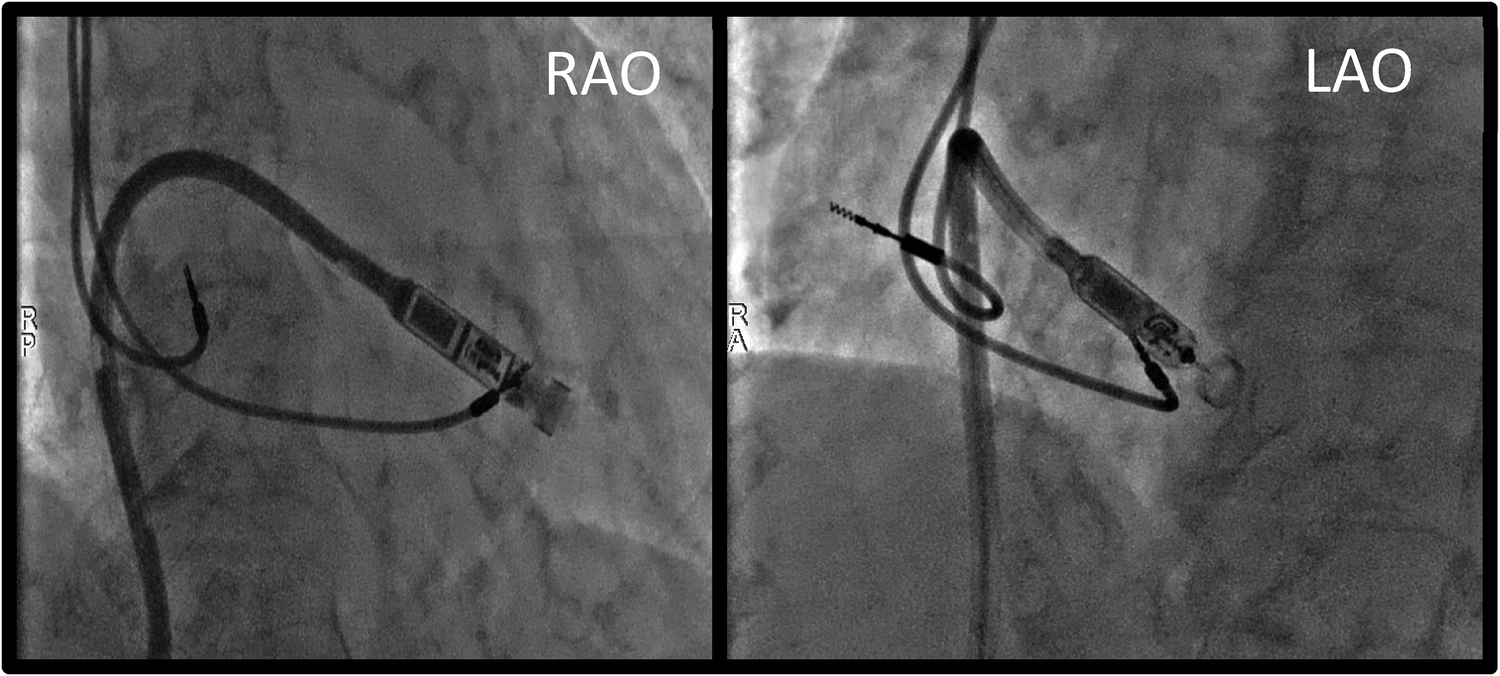

Figure 2

Procedural fluoroscopy images showing leadless PM's position at the level of the lower interventricular septum, just before device deployment. RAO, right anterior oblique; LAO, left anterior oblique.